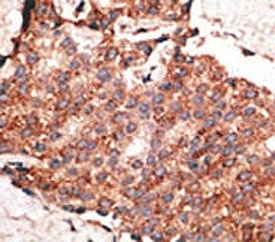

IHC analysis of FFPE human breast carcinoma tissue stained with the BMP1 antibody